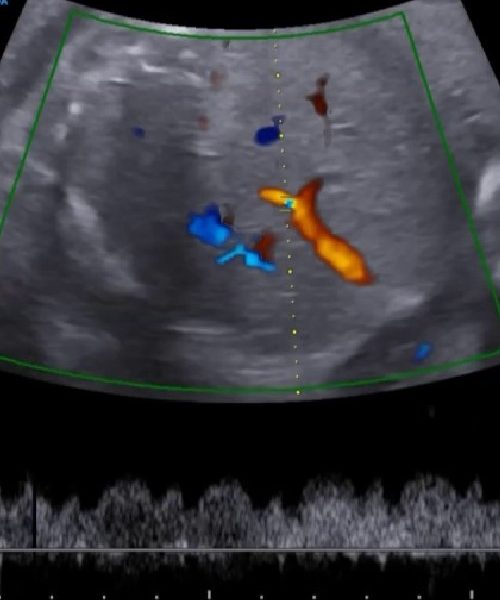

El elegir un centro de especialidad certificado garantiza una evaluación profesional del paciente, así como disponer de informes y resultados confiables. Contamos con la preparación académica en la evaluación mediante la ecografía y medicina fetal, que avala nuestro compromiso con la salud y bienestar de nuestros pacientes. Conozca más.

SERVICIOS DE ESPECIALIDAD

GINECOLOGÍA, PLANIFICACIÓN, EMBARAZO DE ALTO RIESGO, ECOGRAFÍA Y MEDICINA FETAL